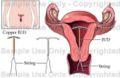

- IUD.jpg 346 × 225; 16 KB